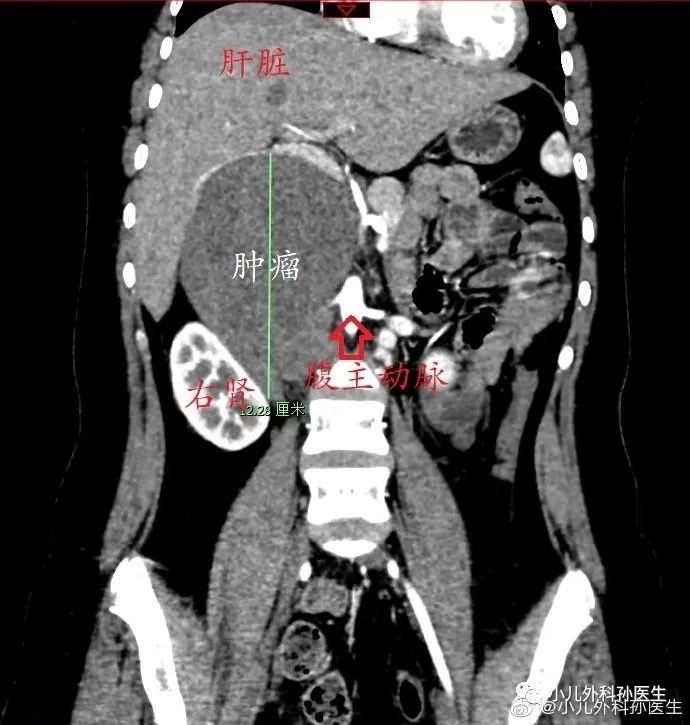

CT检查清晰显示了肿瘤及与周围组织器官的关系。肿瘤起源于腹主动脉和下腔静脉之间,这个位置的肿瘤首先考虑是来自于腹膜后的交感神经节。

肿瘤把下腔静脉推到右侧腹,半包绕了下腔静脉、腹主动脉和右肾动脉,最严重的是完全包绕了左肾静脉,个个都不好惹。